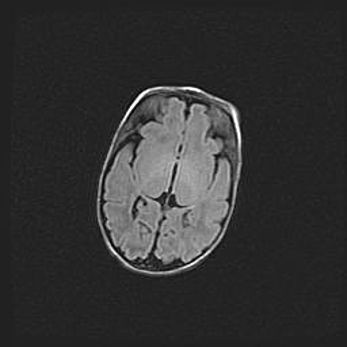

Неполная лизэнцефалия (пахигирия). Открытая гидроцефалия.

Возраст: 17 дней

Вес: 3110 г

Пол: мужской

Окружность головы: 33,5 см

Срок гестации: 35-36 недель

Лизэнцефалия—недоразвитие корковой пластинки и мозговых извилин в результате нарушения миграции нейронов коры. Поверхность мозговых полушарий гладкая. Микроскопически выявляется отсутствие нормальных слоев коры и скопление групп нейронов в подкорковом белом веществе.

Пахигирия—уменьшение числа вторичных извилин. В пораженном полушарии нервные клетки образуют толстый недифференцированный слой с неправильно расположенными нервными волокнами и группами гетеротопных клеток. Нервные клетки незрелые. Белое вещество истончено. При этом нередко аномально развит корково-спинномозговой путь.